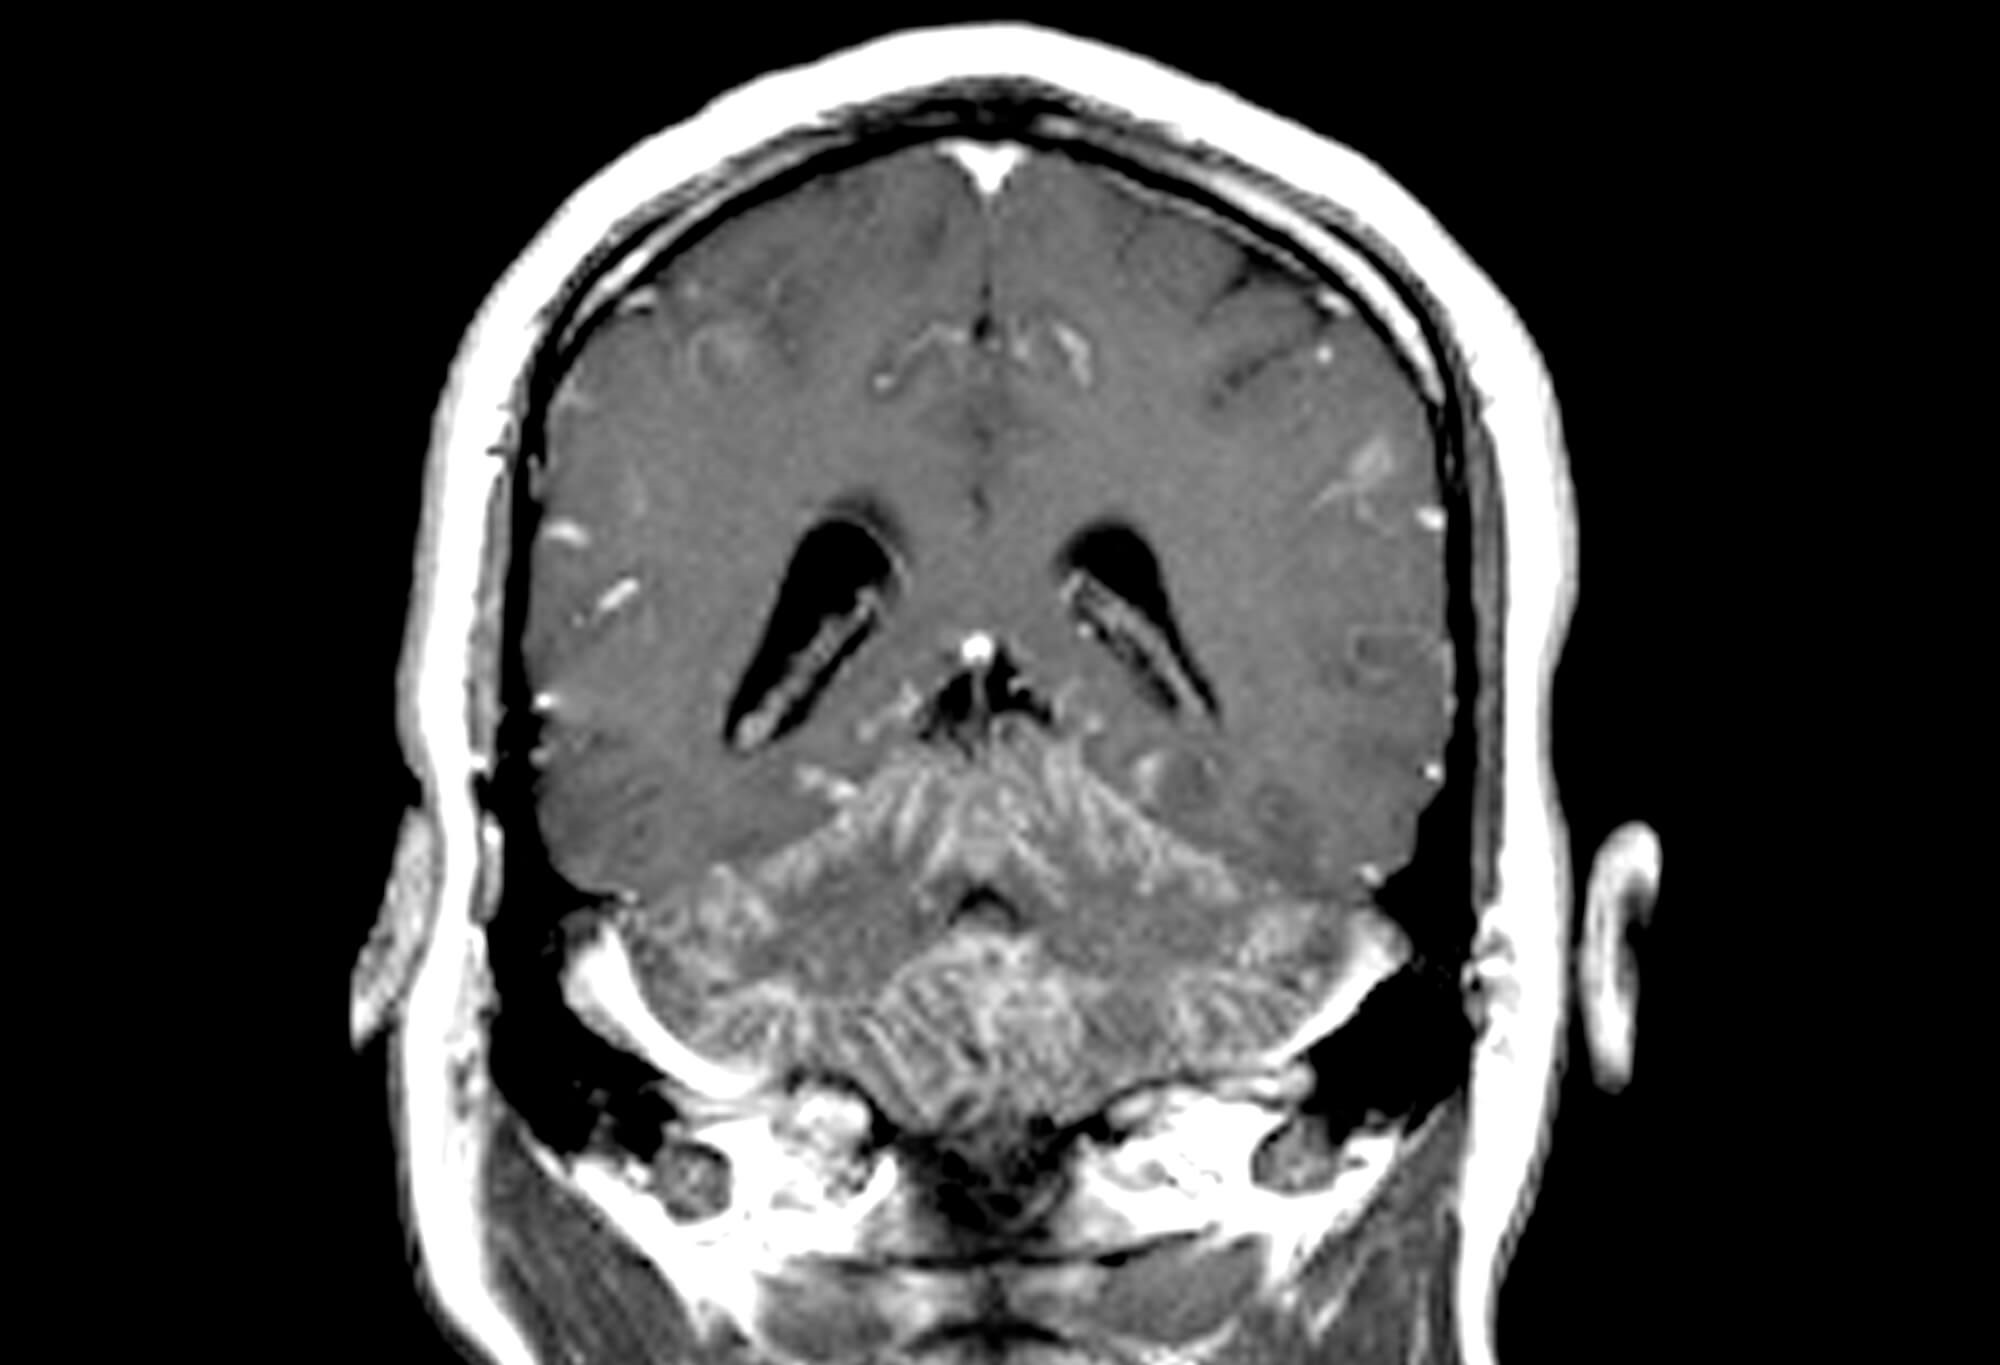

• In cases of suspected CNS sarcoidosis, magnetic resonance imaging (MRI) of the brain and/or cervical, thoracic, or lumbar spine should be conducted, as well as comprehensive CSF analysis. In cases of suspected peripheral nervous system (PNS) sarcoidosis, electromyogram (EMG) and a nerve conduction study (NCS) should be performed, along with nerve or muscle biopsy as clinically indicated.

• Each of the 3 proposed diagnostic categories (possible, probable, and definite) of NS includes the following prerequisite: “The clinical presentation and diagnostic evaluation suggest NS, as defined by the clinical manifestations and MRI, CSF, and/or EMG/NCS findings typical of granulomatous inflammation of the nervous system and after rigorous exclusion of other causes.”